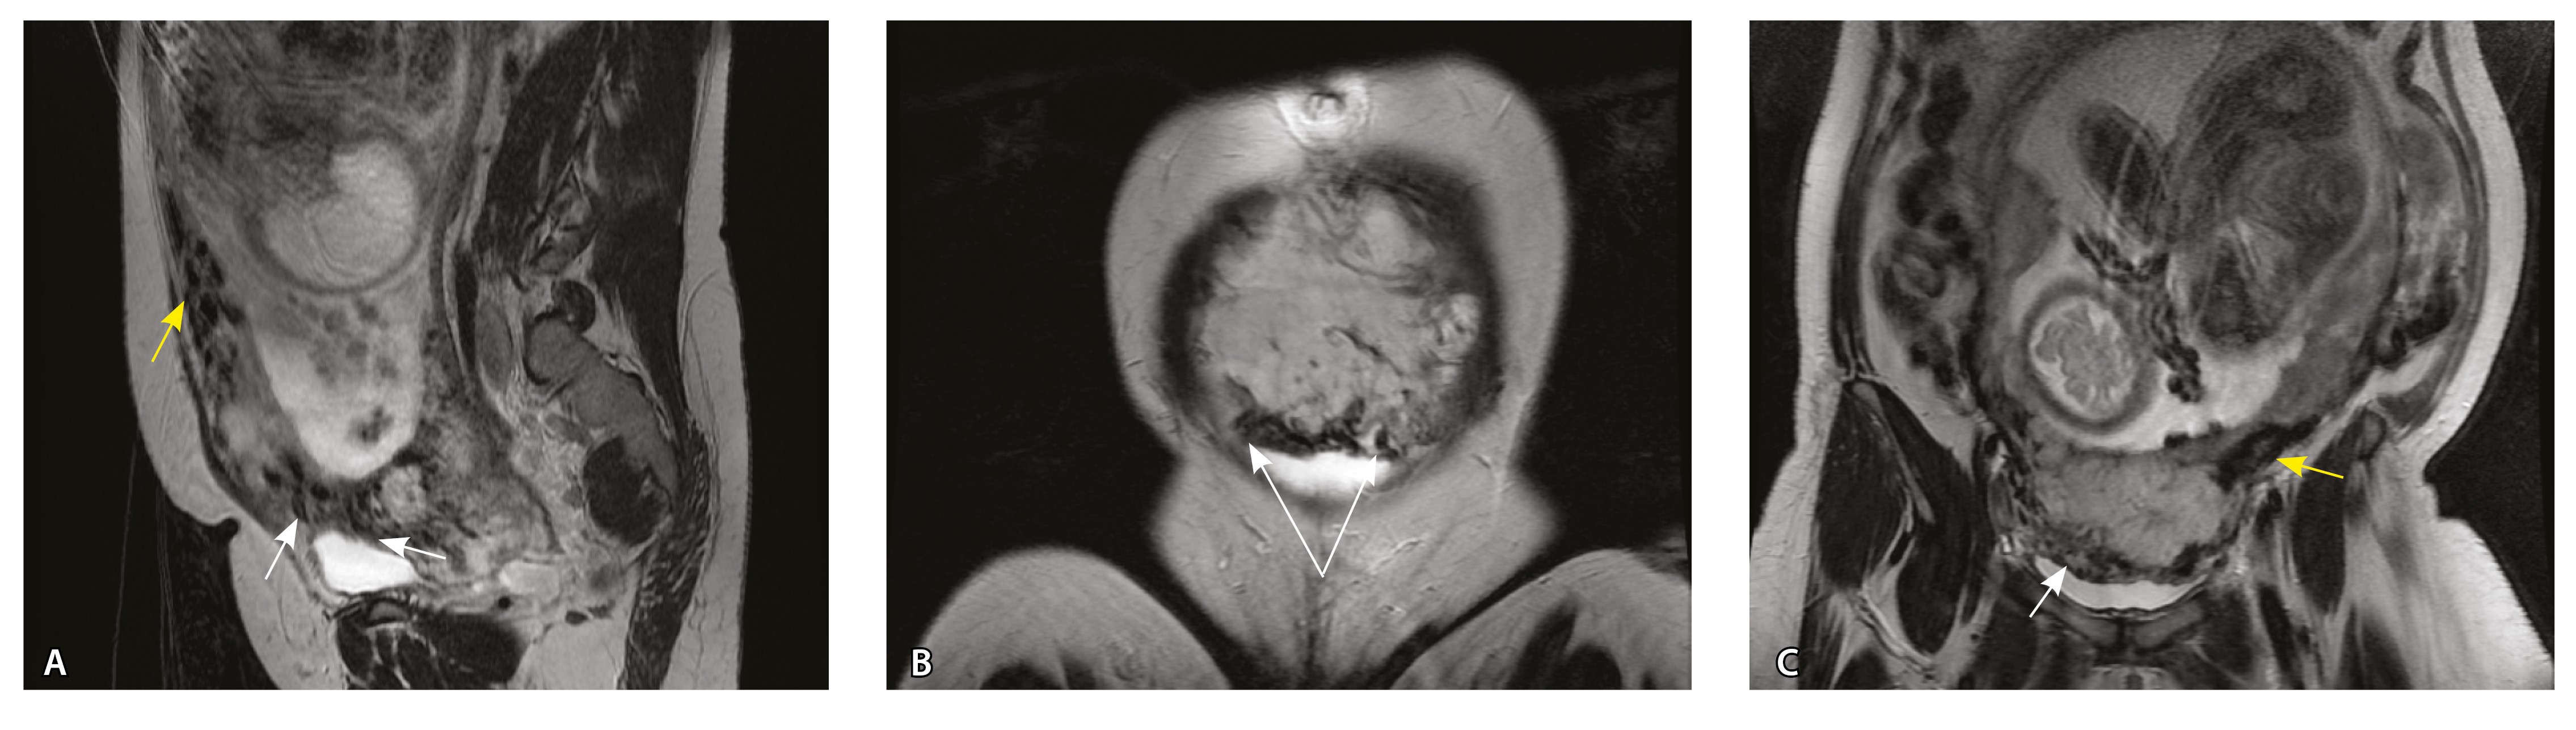

Сосуды 5-го типа. Наличие гиперваскуляризации за пределами матки по данным МРТ, на границе с мочевым пузырем с вовлечением его стенки, сосуды в области перешейка матки, параметрия, в том числе в сочетании с признаками фиброза, наличием рубцово-спаечных изменений и др. Можно предположить, что сосуды 5-го типа являются аналогом pl. рercreta PAS 3b, 3c (рис. 15).

Рис. 15. Беременность 34 недели, pl. percreta, PAS 3b по FIGO (A, Б), PAS 3c по FIGO (В). На магнитно-резонансных томограммах в режиме Т2-взвешенного изображения в сагиттальной (A, В) и аксиальной (Б) плоскостях определяется гиперваскуляризация в области выраженно истонченного нижнего маточного сегмента с распространением сосудов на заднюю стенку мочевого пузыря в области дна (белые стрелки), в область перешейка матки (желтые стрелки)

Данный вариант в патоморфологической картине наиболее сложен для оценки ввиду того, что такие структуры, как параметрий, перешеек матки, стенка мочевого пузыря, обычно не предоставляются в виде макропрепаратов, поэтому визуальные методы, в частности МРТ, могут с большей точностью оценить вовлеченность смежных структур. На микропрепаратах данный вариант инвазии плаценты сочетается с рубцово-спаечными изменениями задней стенки мочевого пузыря с нижним маточным сегментом (рис. 16).